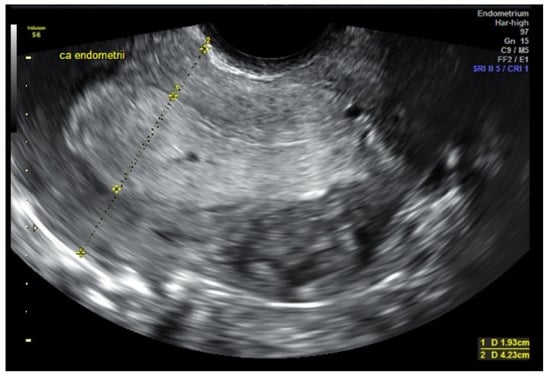

3.1. USG (Ultrasonography) and MRI (Magnetic Resonance Imaging)

- Eriksson, L.S.; Lindqvist, P.G.; Rådestad, A.F.; Dueholm, M.; Fischerova, D.; Franchi, D.; Jokubkiene, L.; Leone, F.P.; Savelli, L.; Sladkevicius, P.; et al. Transvaginal ultrasound assessment of myometrial and cervical stroma invasion in women with endometrial cancer: Interobserver reproducibility among ultrasound experts and gynaecologists. Ultrasound Obstet. Gynecol. 2015, 45, 476–482. [Google Scholar] [CrossRef]

- Capozzi, V.A.; Rosati, A.; Rumolo, V.; Ferrari, F.; Gullo, G.; Karaman, E.; Karaaslan, O.; HacioĞlu, L. Novelties of ultrasound imaging for endometrial cancer preoperative workup. Minerva Med. 2021, 112, 3–11. [Google Scholar] [CrossRef] [PubMed]

- Epstein, E.; Van Holsbeke, C.; Mascilini, F.; Måsbäck, A.; Kannisto, P.; Ameye, L.; Fischerova, D.; Zannoni, G.; Vellone, V.; Timmerman, D.; et al. Gray-scale and color Doppler ultrasound characteristics of endometrial cancer in relation to stage, grade and tumor size. Ultrasound Obstet. Gynecol. 2011, 38, 586–593. [Google Scholar] [CrossRef]

- Fischerova, D.; Frühauf, F.; Pinkavova, I.; Kocián, R.; Nemejcova, K.; Dusek, L.; Cibula, D. Factors affecting sonographic preoperative local staging of endometrial cancer. Ultrasound Obstet. Gynecol. 2014, 43, 575–585. [Google Scholar] [CrossRef]

- Sawicki, W.; Spiewankiewicz, B.; Stelmachów, J.; Cendrowski, K. The value of ultrasonography in preoperative assessment of selected prognostic factors in endometrial cancer. Eur. J. Gynaecol. Oncol. 2003, 24, 293–298. [Google Scholar]